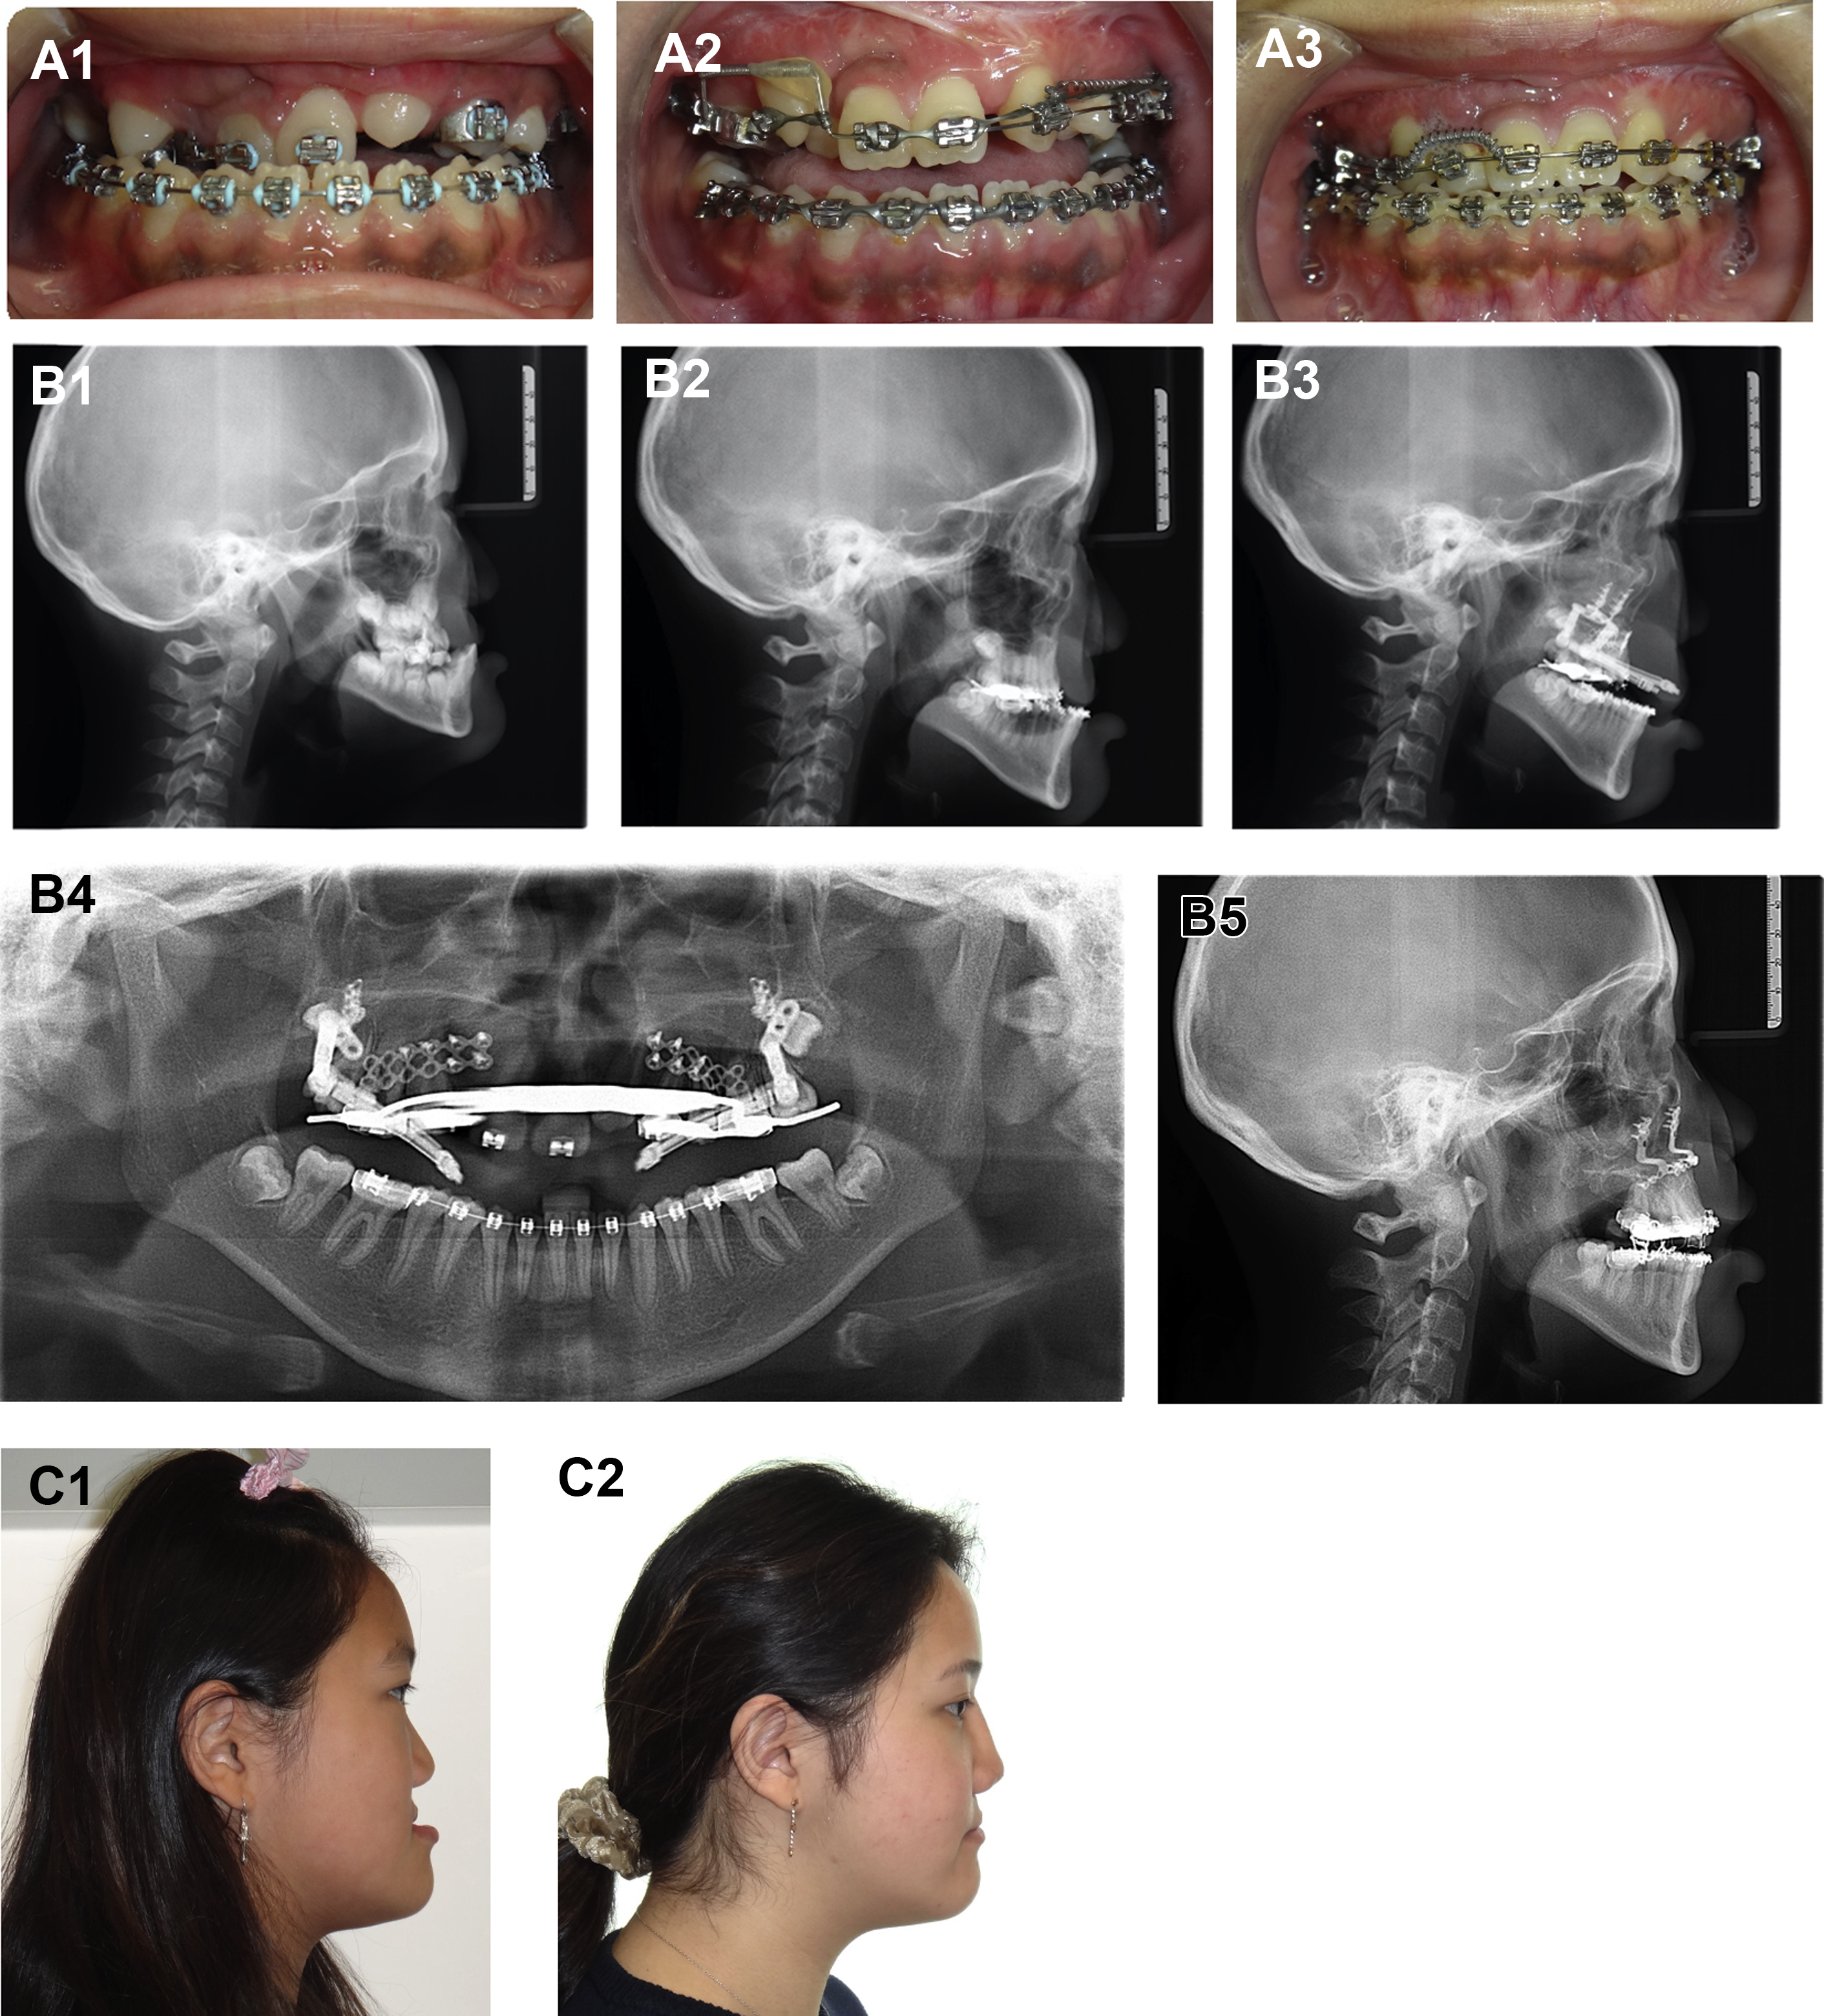

Early and active involvement of the orthodontist, frequent and serial evaluation, and close communication between the orthodontist and surgeon are crucial to executing a successful treatment plan. Predistraction orthodontics, orthodontic manipulation during the activation and consolidation phases, and postdistraction orthodontic management are all phases to be considered when planning maxillary distraction (see Fig. 3 A1–A3). ,

The goal of Le Fort I distraction is the restoration of class I occlusion. The final position of the maxilla required to restore occlusion is determined by the orthodontic and surgical team. A treatment plan for orthodontic preparation with the goals of leveling, aligning, and coordinating the maxillary and mandibular arches is crafted by the orthodontic team executed with close clinical follow-up. Determining the final position of the maxilla and final occlusion is done with a combination of physical examination, dental models, photographs, three-dimensional computed tomographic imaging, and cephalometric analysis. Continuity of the maxillary arch should be ensured before performing maxillary distraction. Alveolar clefts, when present, should be reconstructed with bone graft and the continuity of the maxillary arch confirmed clinically and radiographically before maxillary distraction. The presence of an alveolar cleft or unidentified fracture through the grafted site can lead to an unstable maxilla (two-piece maxilla with separation at the cleft site) during osteotomy and device activation.